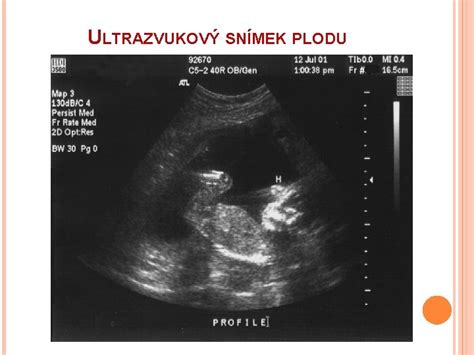

Ultrazvukové Vyšetrenia

- - 12. týždeň

- - 22. týždeň (prvý ultrazvukový screening)

- - 32. týždeň